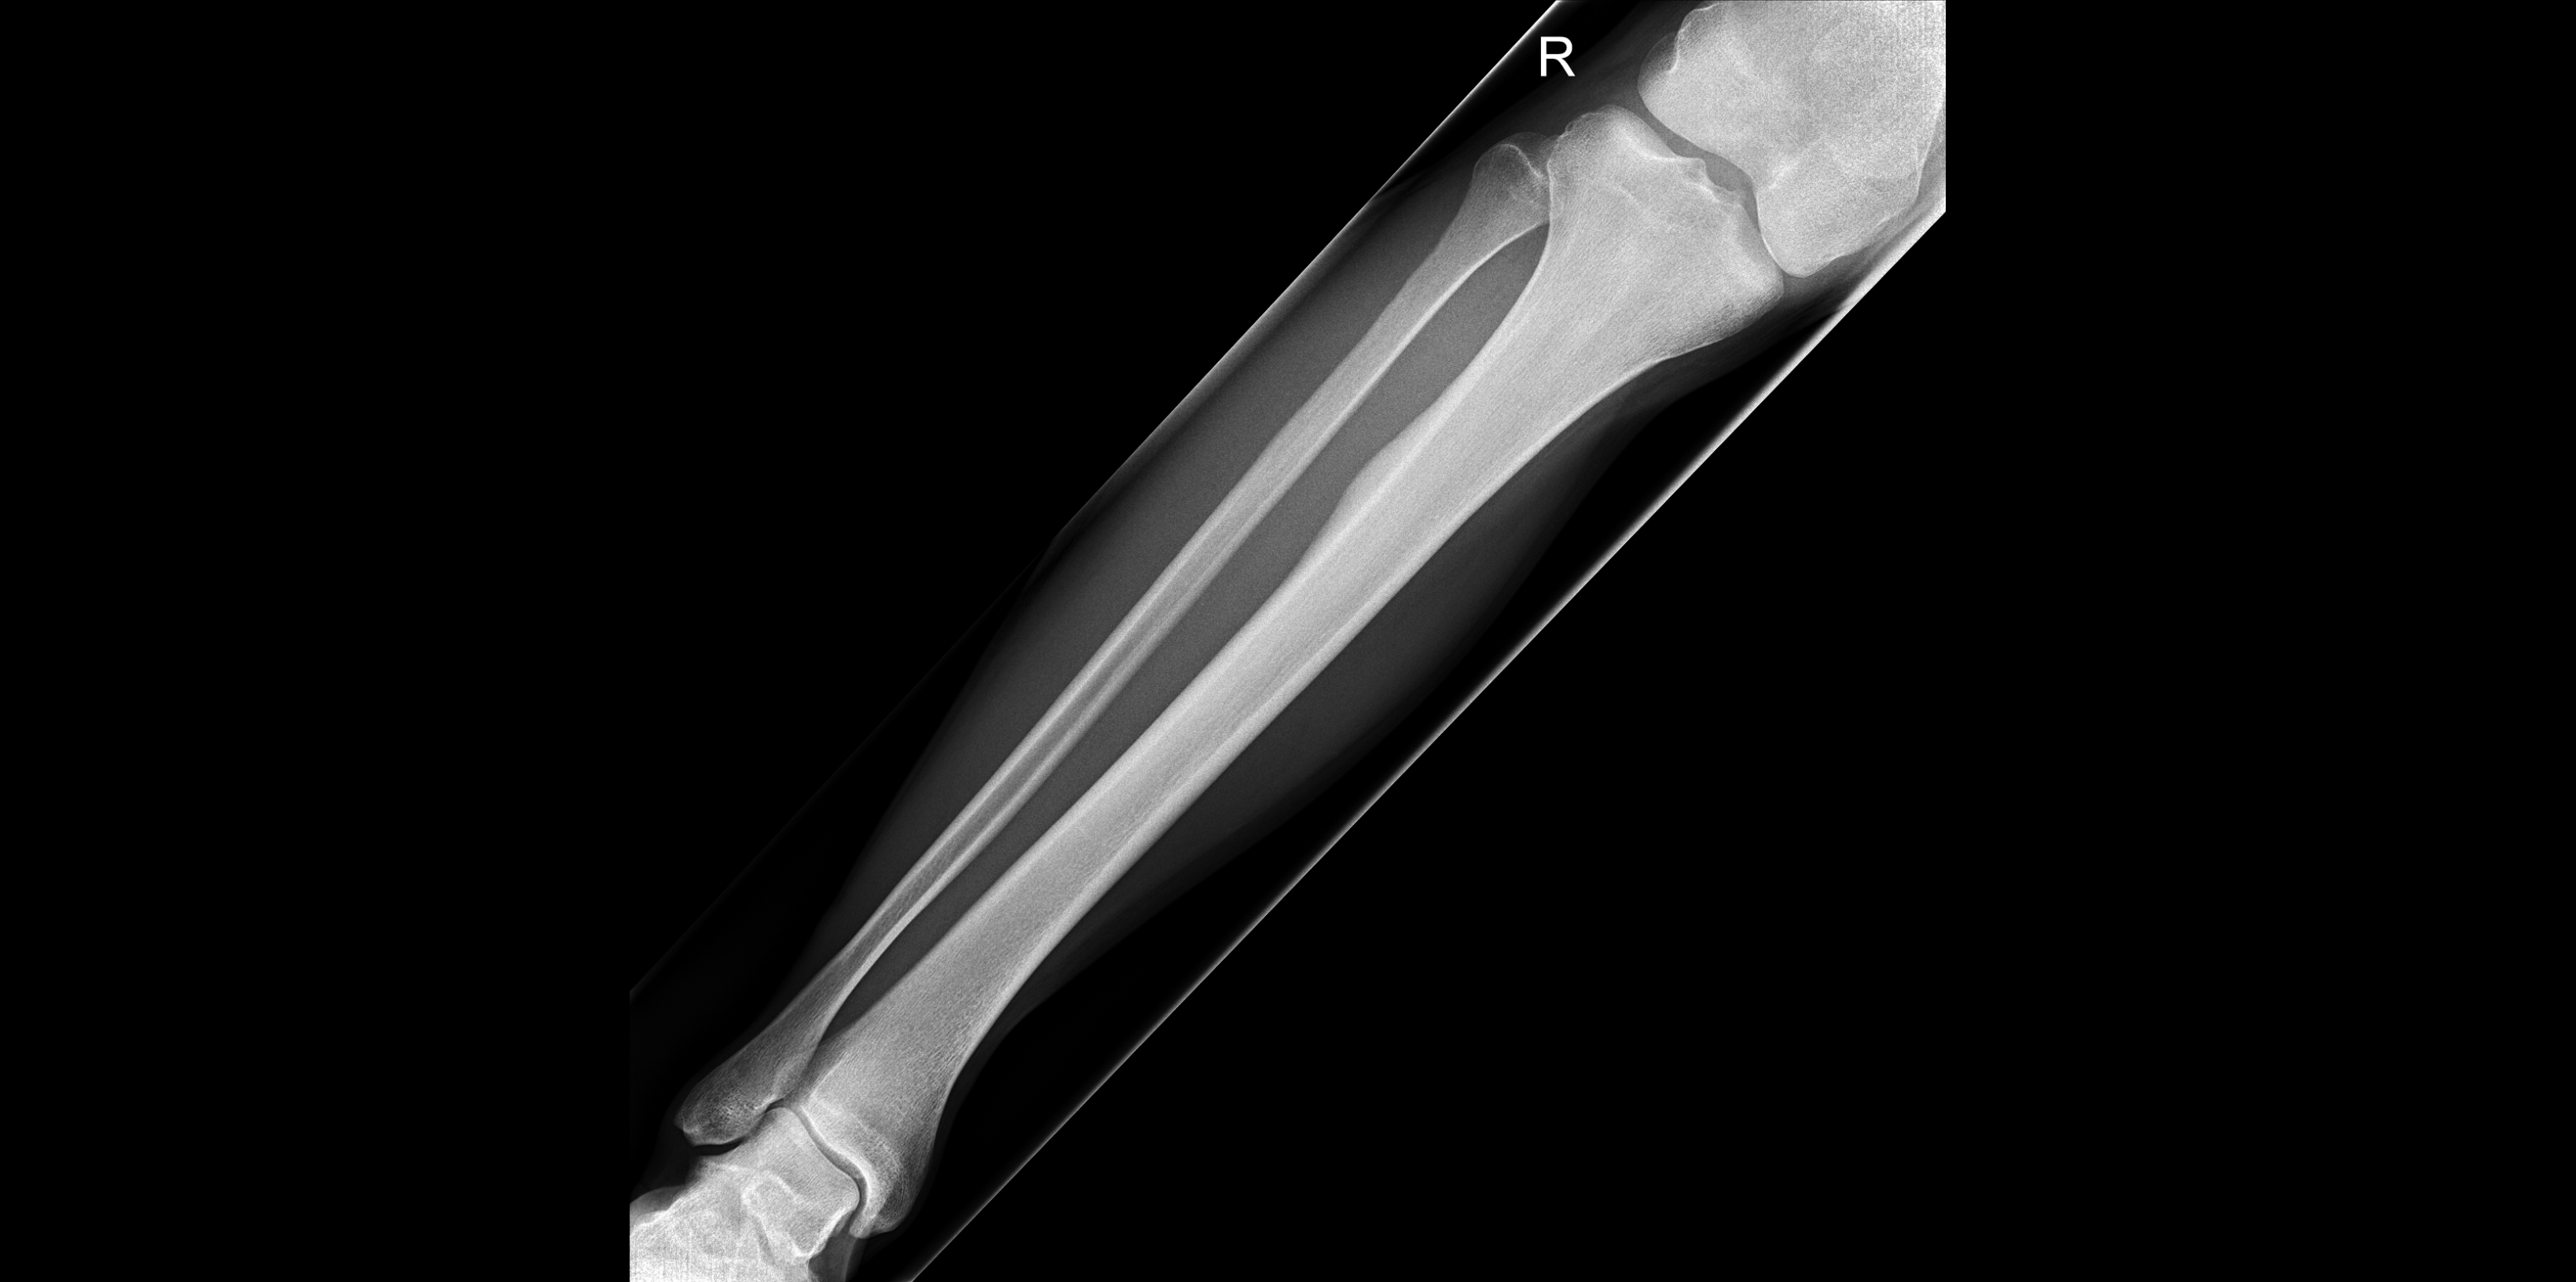

Daneben gibt es jedoch auch Menschen die ohne. Met een speciale röntgentechniek kan worden gekeken of er sprake is van een breuk door overbelasting Shin splints zijn geassocieerd met herhaaldelijke overbelasting van het bindweefsel dat de scheenbenen omringd maar de exacte oorzaak is eigenlijk niet geweten. Die Beschwerden treten vorwiegend abends oder nachts auf und zwar verstärkt im Ruhezustand also im Liegen oder Sitzen.

Een Jonge Man Met Nachtelijke Pijn In Een Scheenbeen Nederlands Tijdschrift Voor Geneeskunde